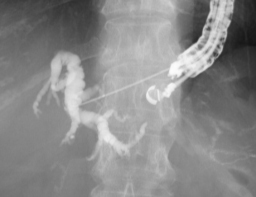

実際の症例をお示します。患者さんは膵癌により胆管が詰って黄疸が出現しました。膵癌が十二指腸へ広がり内腔が狭くなったため、内視鏡が通過せず、通常のERCPによるステント留置が不可能でした。そのためEUS-BDを施行しました。胃内から超音波内視鏡で肝臓の中の胆管を観察して、胆管を穿刺します(図1)。胆管に造影剤を満たし(図2)、ガイドワイヤーを挿入し、胆管金属ステントを留置しました(図3,4)。この手技により、体内にチューブを埋め込む形で胆汁の流れを確保することができ、黄疸は改善しました。

図2図2